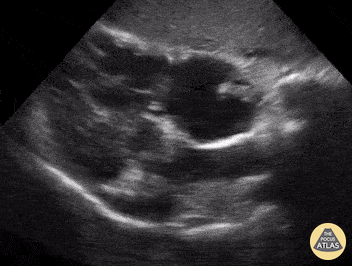

Prominent Finding(s) seen in this RUQ clip:

Ascites and Pleural Effusion with Jellyfish sign